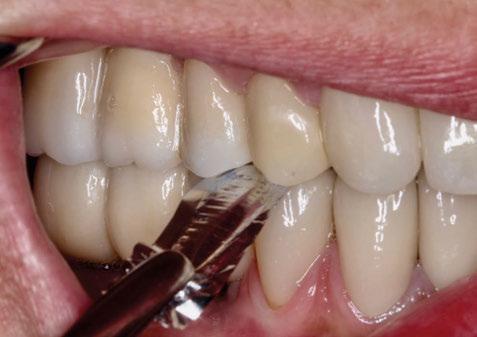

Seguidamente, se colocaron los pilares cónicos TSV-TM de Zimmer® y se atornillaron los pilares provisionales de titanio (Figuras 17-23).

4. Fase protésica provisional

Una vez colocados los pilares provisionales de titanio, se adaptó la férula pick-up modificada y se verificó su correcto asentamiento de los pilares a través de los orificios de ésta. A continuación, se recapturó la férula a los pilares de titanio mediante resina acrílica autopolimerizable (Enamel Temp

Plus®) y, una vez polimerizada, se tomó un registro de mordida, se desatornillaron los pilares y se retiraron de boca. Seguidamente, se atornillaron los análogos verificando que no hubiera movilidad de ningún pilar y se envió al laboratorio para el acabado y pulido final, eliminando todo el soporte y añadiendo un refuerzo metálico por palatino. En boca, se colocaron los tapones de cicatrización de los transepiteliales y se le explicaron las recomendaciones postquirúrgicas y medicación necesaria. Instruimos al laboratorio a dejar los perfiles de emergencia lo más estrechos posibles y los pónticos ovoides entrando unos 3 mm en cada alveolo a fin de preservar la arquitectura gingival presente.

A las 24 horas se citó al paciente nuevamente, se atornilló el provisional en boca y se realizó una

ortopantomografía de verificación del ajuste pasivo de todos los implantes. Por último, tapamos las chimeneas con teflón y resina provisional y se chequeó nuevamente la oclusión, dando nuevamente las instrucciones de higiene y mantenimiento de la prótesis provisional (Figuras 24-27).